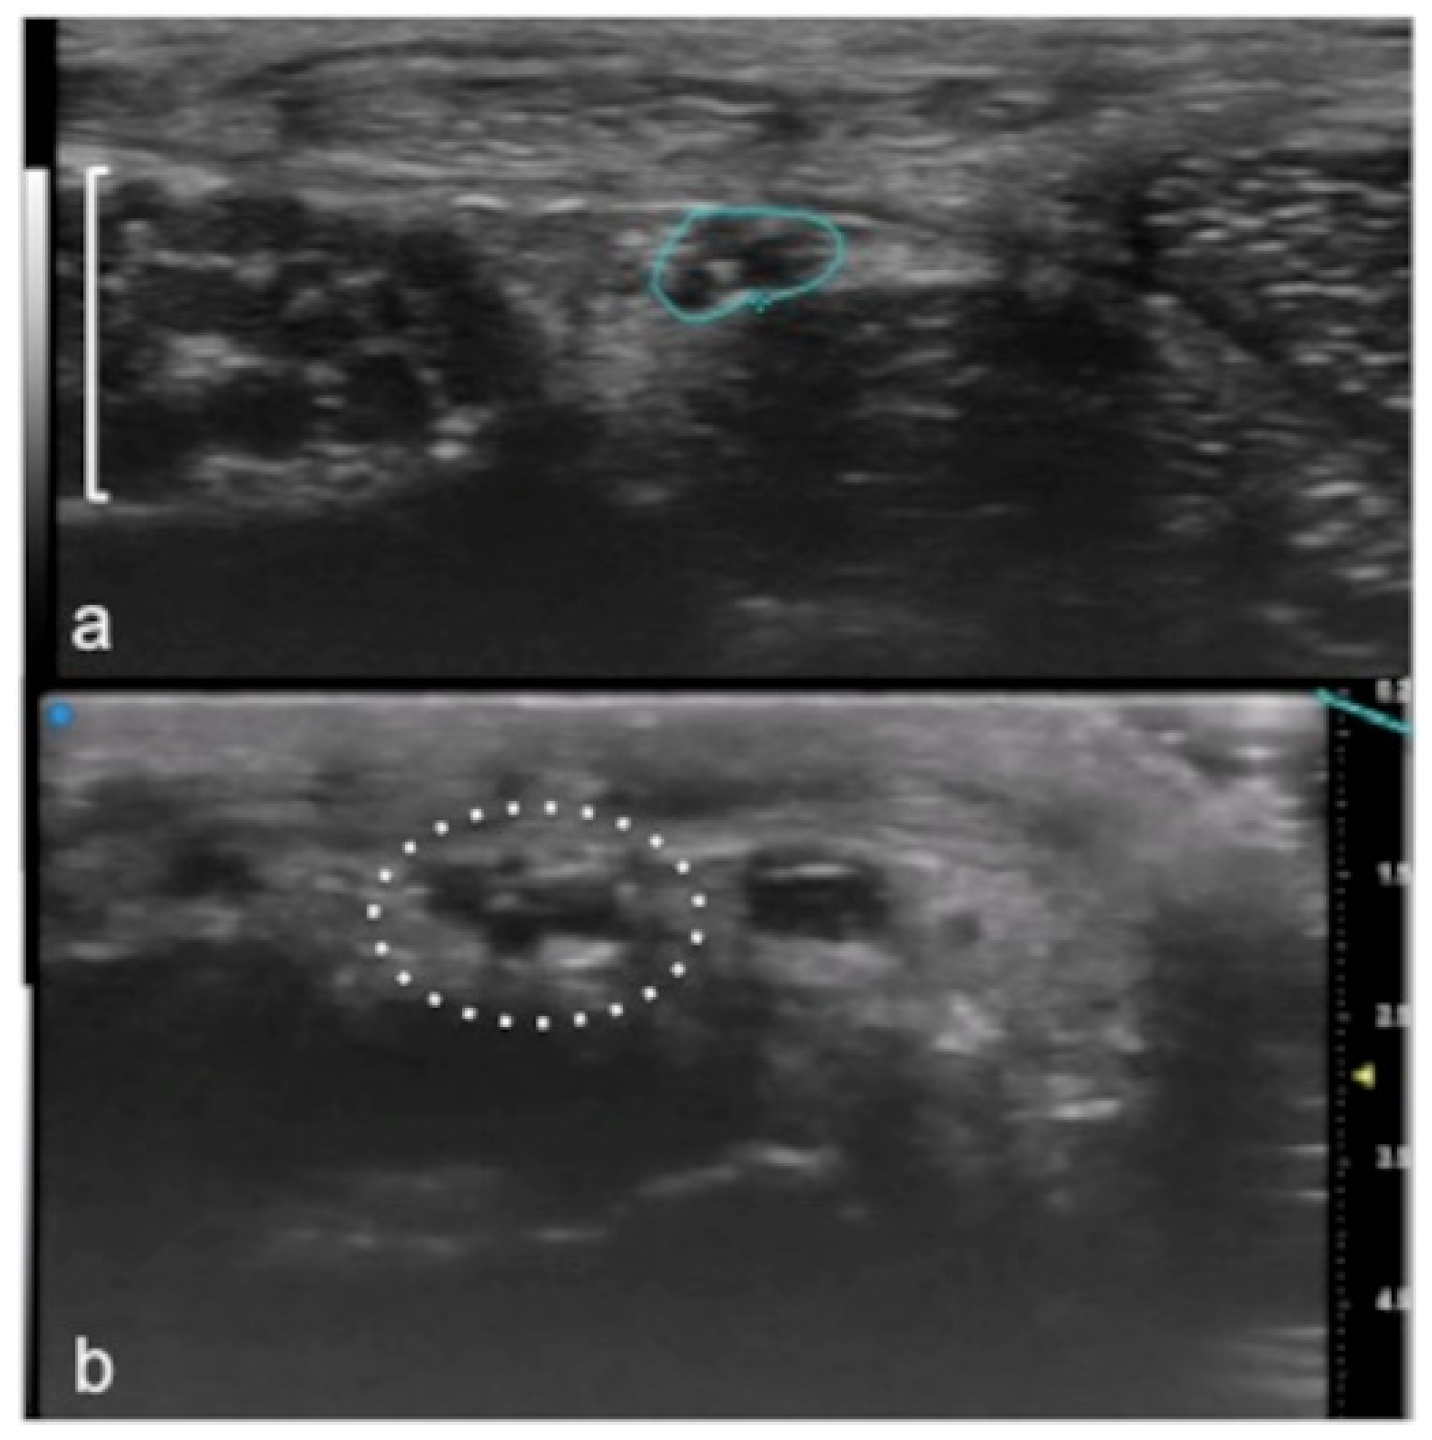

UHFUS could represent an advantageous technique for the identification of small and soft-tissue neoformations such as glomus tumors (Figure 11 and Figure 12).

Figure 11.

Glomus tumor. The location corresponds to the pulp of finger IV (a). The patient had the classical triad of symptoms: paroxysmal pain, pinpoint pain, and cold hypersensitivity, lasting for two years. In (b), UHFUS shows a well-delimited nodule in contact with the adjacent phalangeal bone (arrowhead), but no cortical deformity is present. No significant hyperemia on color Doppler was noticed. On CUS (c), the nodule was delineated only thanks to the help of the preliminary UHFUS exam.

Figure 12.

Glomus tumor in the subungual space. No clear alterations were visible during clinical examination at the site of pain (circle in (a)). In (b), UHFUS effectively demonstrates the presence of a hypo-isoechogenic nodule (calibers) in contact with the adjacent phalangeal bone (arrowhead) under the nail plate (arrows). Note the small deformation of the nail plate. Mild vascularization on color Doppler was present (c).

Glomus tumors are rare, benign, vascular neoplasms arising from the glomus body, which is a contractile neuromyoarterial structure found in the reticular dermis. This structure controls blood pressure and temperature by regulating blood flow in the cutaneous vasculature. Hyperplasia in any of these parts can lead to tumor formation, which is extremely painful. Glomus tumors account for 1–5% of soft-tissue tumors of the hand, and 75% of them are subungual in location. Other less commonly involved sites in the hand are the nail matrix, nail bed, and pulp of the finger. The delay in diagnosing these tumors for many years is a significant problem. It is not uncommon that patients are easily misdiagnosed with conditions such as neuropathic complaints, arthritis, or neuralgia and undergo unsuitable treatment. For these reasons, when the clinical examination is equivocal, noninvasive imaging techniques may be needed to aid in the diagnosis and delineate the anatomy preoperatively. Complete surgical excision of the tumor is the only effective treatment. Incomplete excision is considered the main cause of recurrence. US follow-up and/or intraoperative US may be useful for reducing recurrence and ensuring adequate resection, and the UHFUS tool is promising in this field [56].